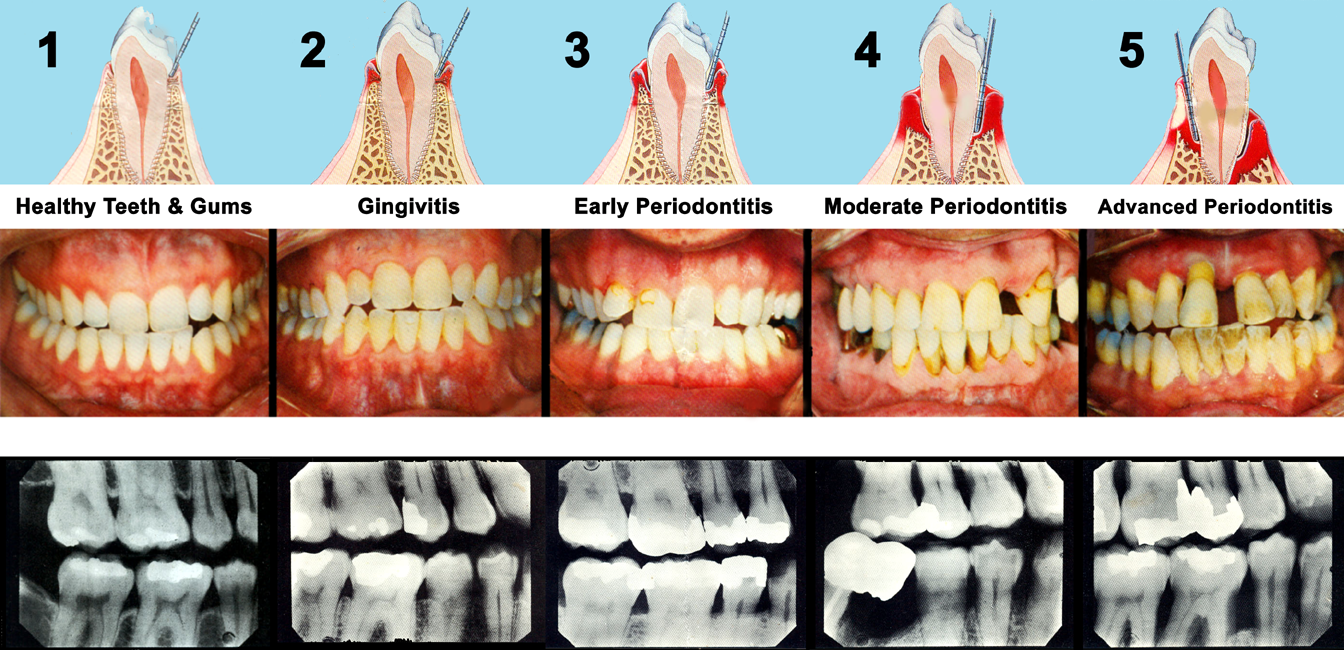

Periodontal Disease Waterbury CT